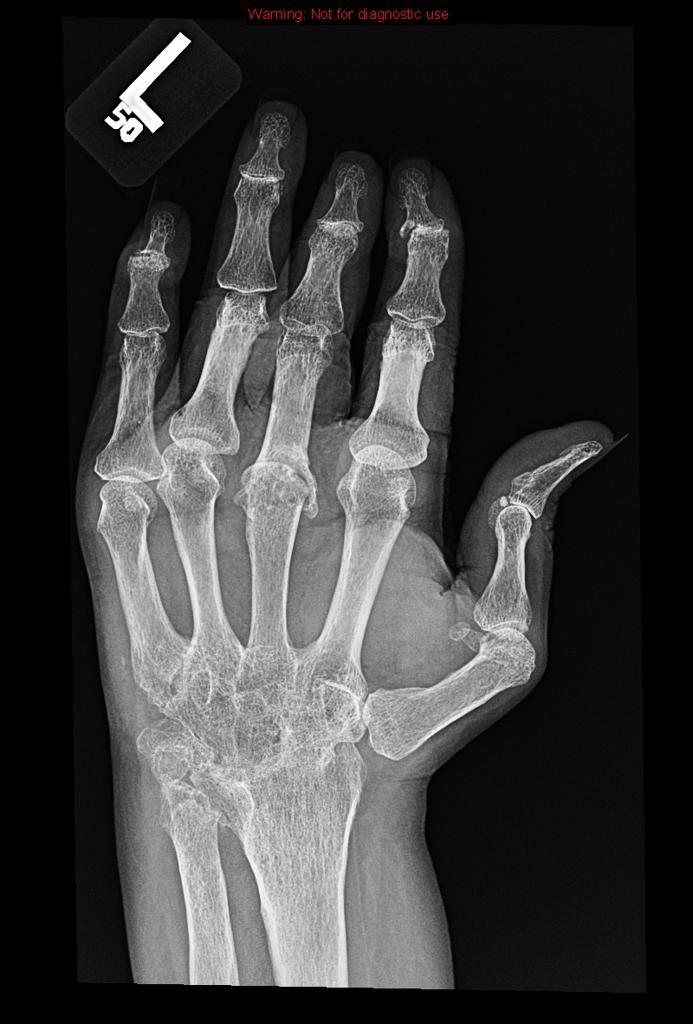

Radiographic hallmarks of RA

Earliest radiographic findings of RA

soft tissue swelling and peri-articular osteopenia (reflects synovitis and hyperemia)

First erosions to occur in the hand in RA patients

Bad RA in the hands

RA